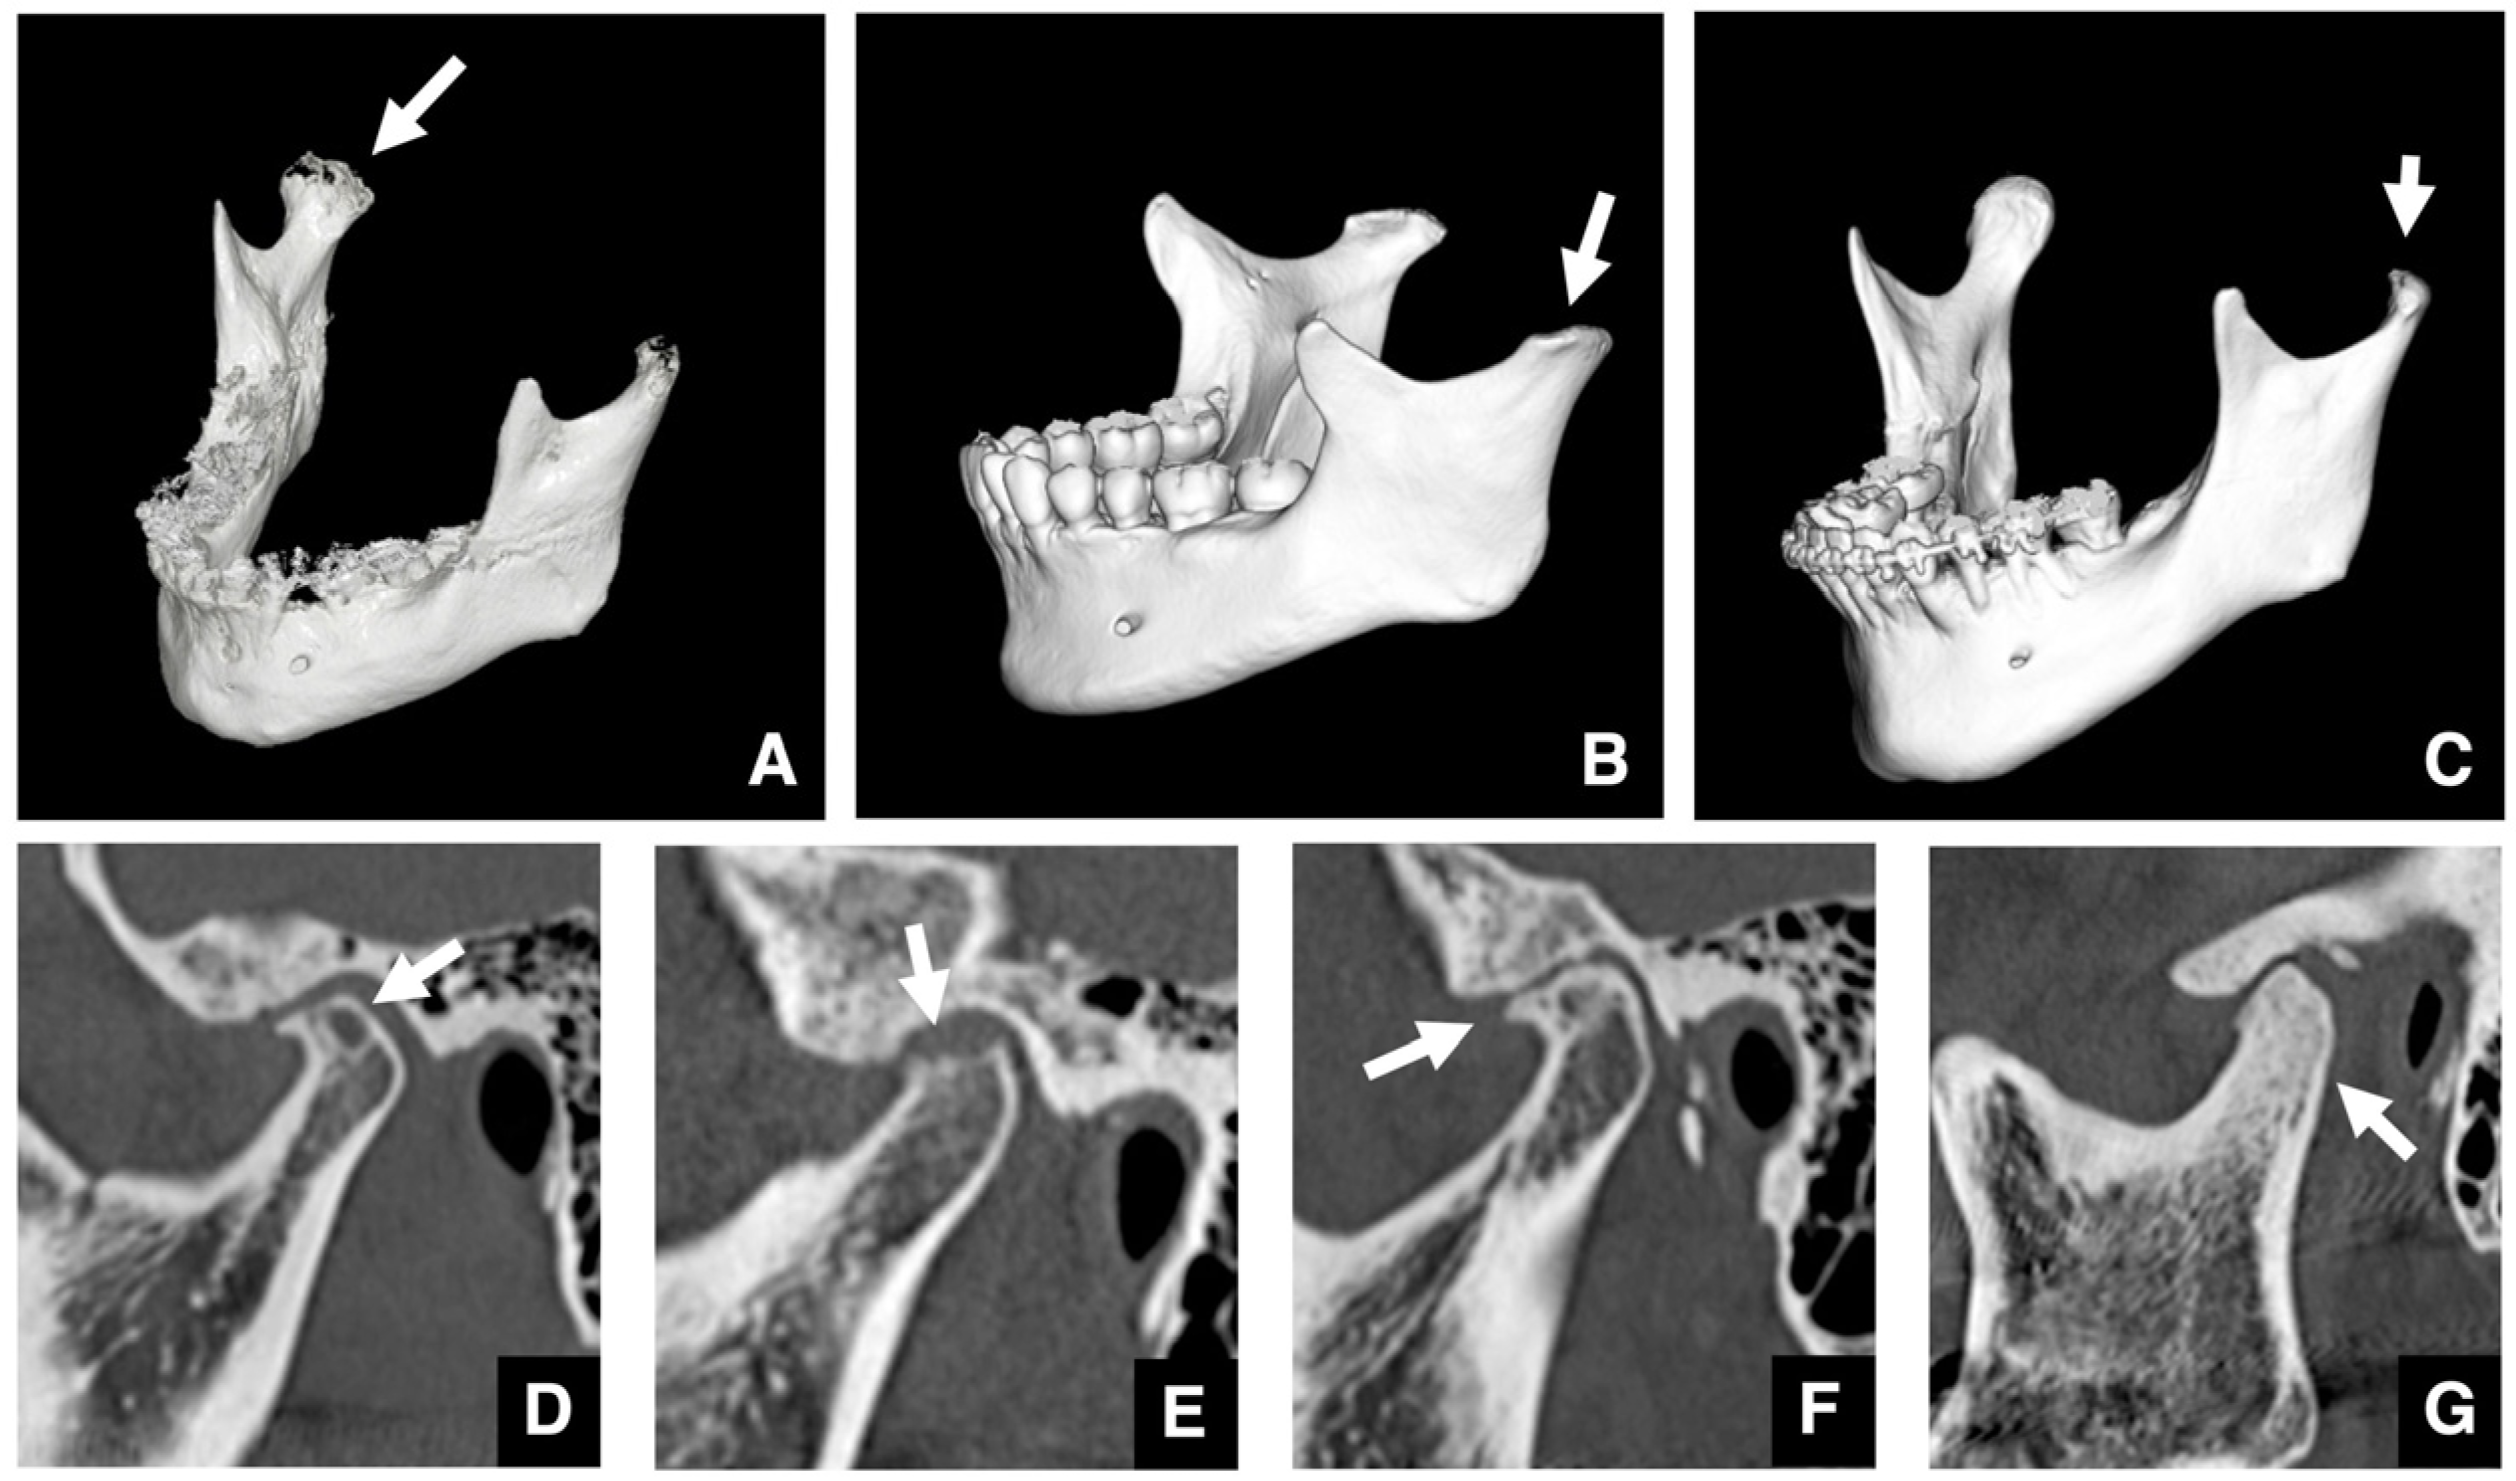

| Setting the osteotomy line 1. Evaluation of the position of the mandibular canal and surrounding bone quality Presence or absence of mandibular canal bifurcation and course of resection site Distance from the buccal wall of the mandibular canal to the buccal cortical bone margin Bone quality around the mandibular canal (CT number) 2. Distance from the mandibular notch to the lingula Whether it is 14 mm or more 3. Morphology of the mandible and variation in cortical bone thickness Cortical bone thickness in the medial osteotomy area and lateral osteotomy area Enhanced safety through improved visibility 1. Medial curvature of the mandibular ramus Mandibular ramus is straight or strong curvature 2. Course of small blood vessels along the bone surface Depression of the buccal-lingual cortical bone from the mandibular fossa to the mandibular ramus region, trabecular bone defect Improved success rates through enhanced postoperative bone integration 1. Degree of interference between bone segments The presence or absence of interference between the proximal and distal bone segments formed during virtual mandibular deformity surgery |